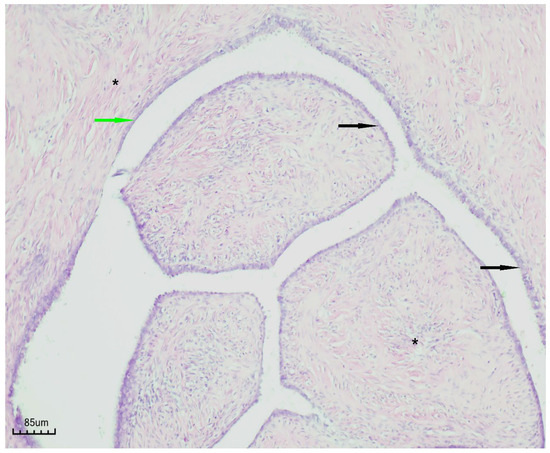

3.7. Histopathological Findings

Histopathological examination revealed a cystic lesion characterized by branching papillary projections of variable size. The papillae and intervening spaces were lined predominantly by simple to pseudostratified cuboidal or columnar epithelium, with only focal areas of stratification. Ciliated epithelial features were occasionally observed in a focal distribution. The underlying stroma consisted of a proliferation of bland spindle cells arranged mainly in fascicles. Importantly, no evidence of epithelial atypia or stromal invasion was identified (Figure 5 and Figure 6).

Figure 6. Papillary serous cystadenofibroma (H&E staining, ×100). The cystic wall is indicated by the green arrow, the simple-to-pseudostratified epithelium by the black arrow, and the fibrous stroma by the black asterisk.